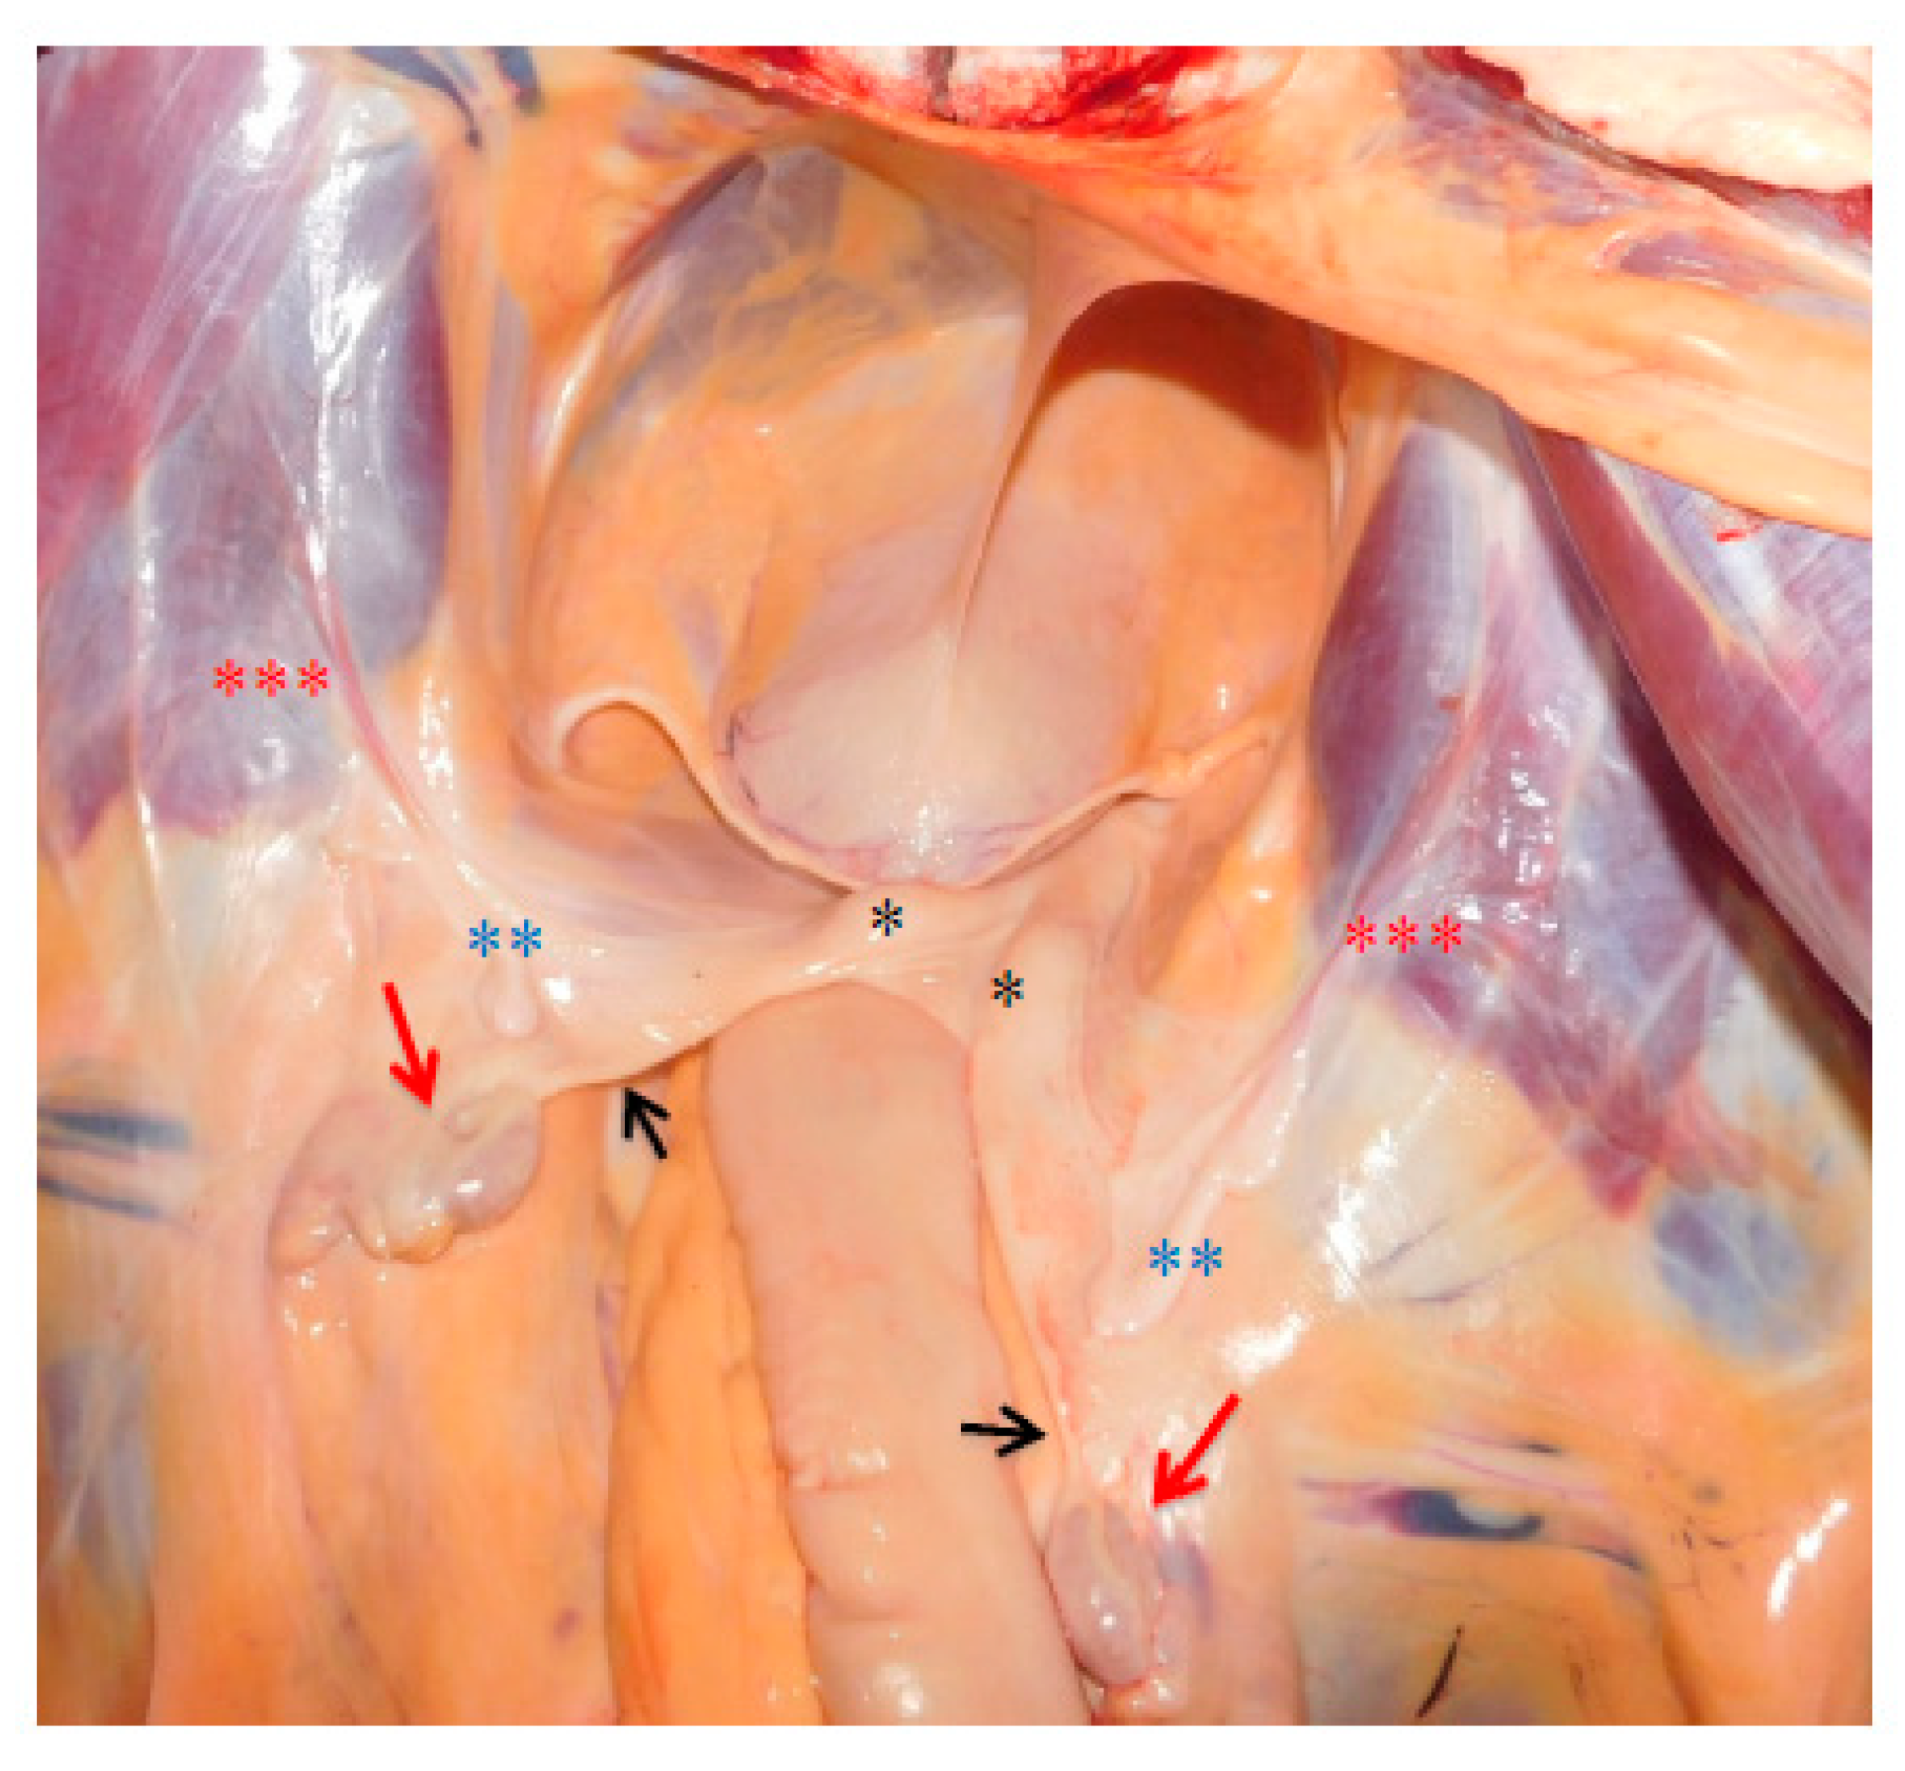

3.3. Necropsy and Anatomopathological Examination